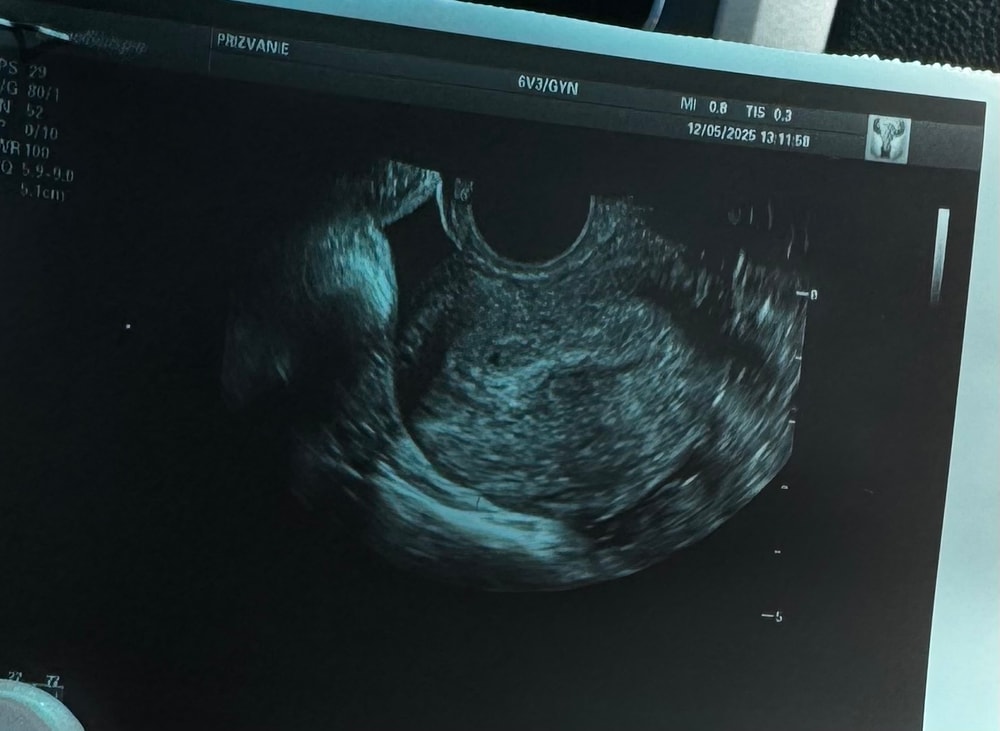

Первое узи

Рано пошли на УЗИ.У меня первый день последних месячных-1 апреля.На данный момент акушерский срок 5 недель 6 дней.На узи записана на 31 мая.Раньше там делать нечего.

Наверное вы рано сходили. Я в 4 недель 6 дней по месячным ходила на узи. Там маленький кругляшок был на узи.

Потому что очень рано,на таком сроке ставят беременность? и все. У меня меньше вас на 2 дня,я только в конце месяца записалась

Очень, очень рано пошли. Идите в 7-8 недель

Очень похоже, что у вас очень маленький срок, повторите узи через недели 2